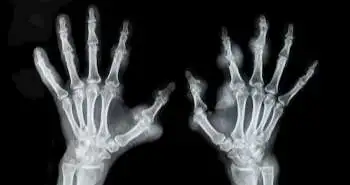

Physical and ultrasound methods for predicting disease activity in RA patients

Rheumatoid arthritis is a chronic autoimmune disease manifested by inflammation in synovial tissue and destruction of articular components, which in case if not controlled properly, can lead to disability in patients. Therefore, it's very important to analyse the activity and control of this disease. In recent years’ sonography use is on the rise for the evaluation of disease activity.

The purpose of this study was to compare “clinical examination” and “ultrasonography” methods for the detection of disease activity in patients with rheumatoid arthritis.

This cross-sectional study was conducted during 2015 in Al-Zahra Hospital of Isfahan. 90 patients diagnosed with rheumatoid arthritis by rheumatologist participated in the study, based on American College of Rheumatology 2010 criteria. All patients, collaborator by radiologists were subjected to sonography of specific joints structures using two methods, i.e., high-resolution ultrasonography and power Doppler.

During study total of 2520 joints from 90 patients were examined physically and through ultrasonography. 244 joints (9.7%) were detected in physical examination. 348 joints (13.4%) were detected by ultrasonography. The frequency of joints involvement between the two groups was different in physical examination and ultrasonography (P < 0.001).

So the study concludes that probably ultrasonography can diagnose joint involvement better than physical examination in patients with Rheumatoid arthritis.